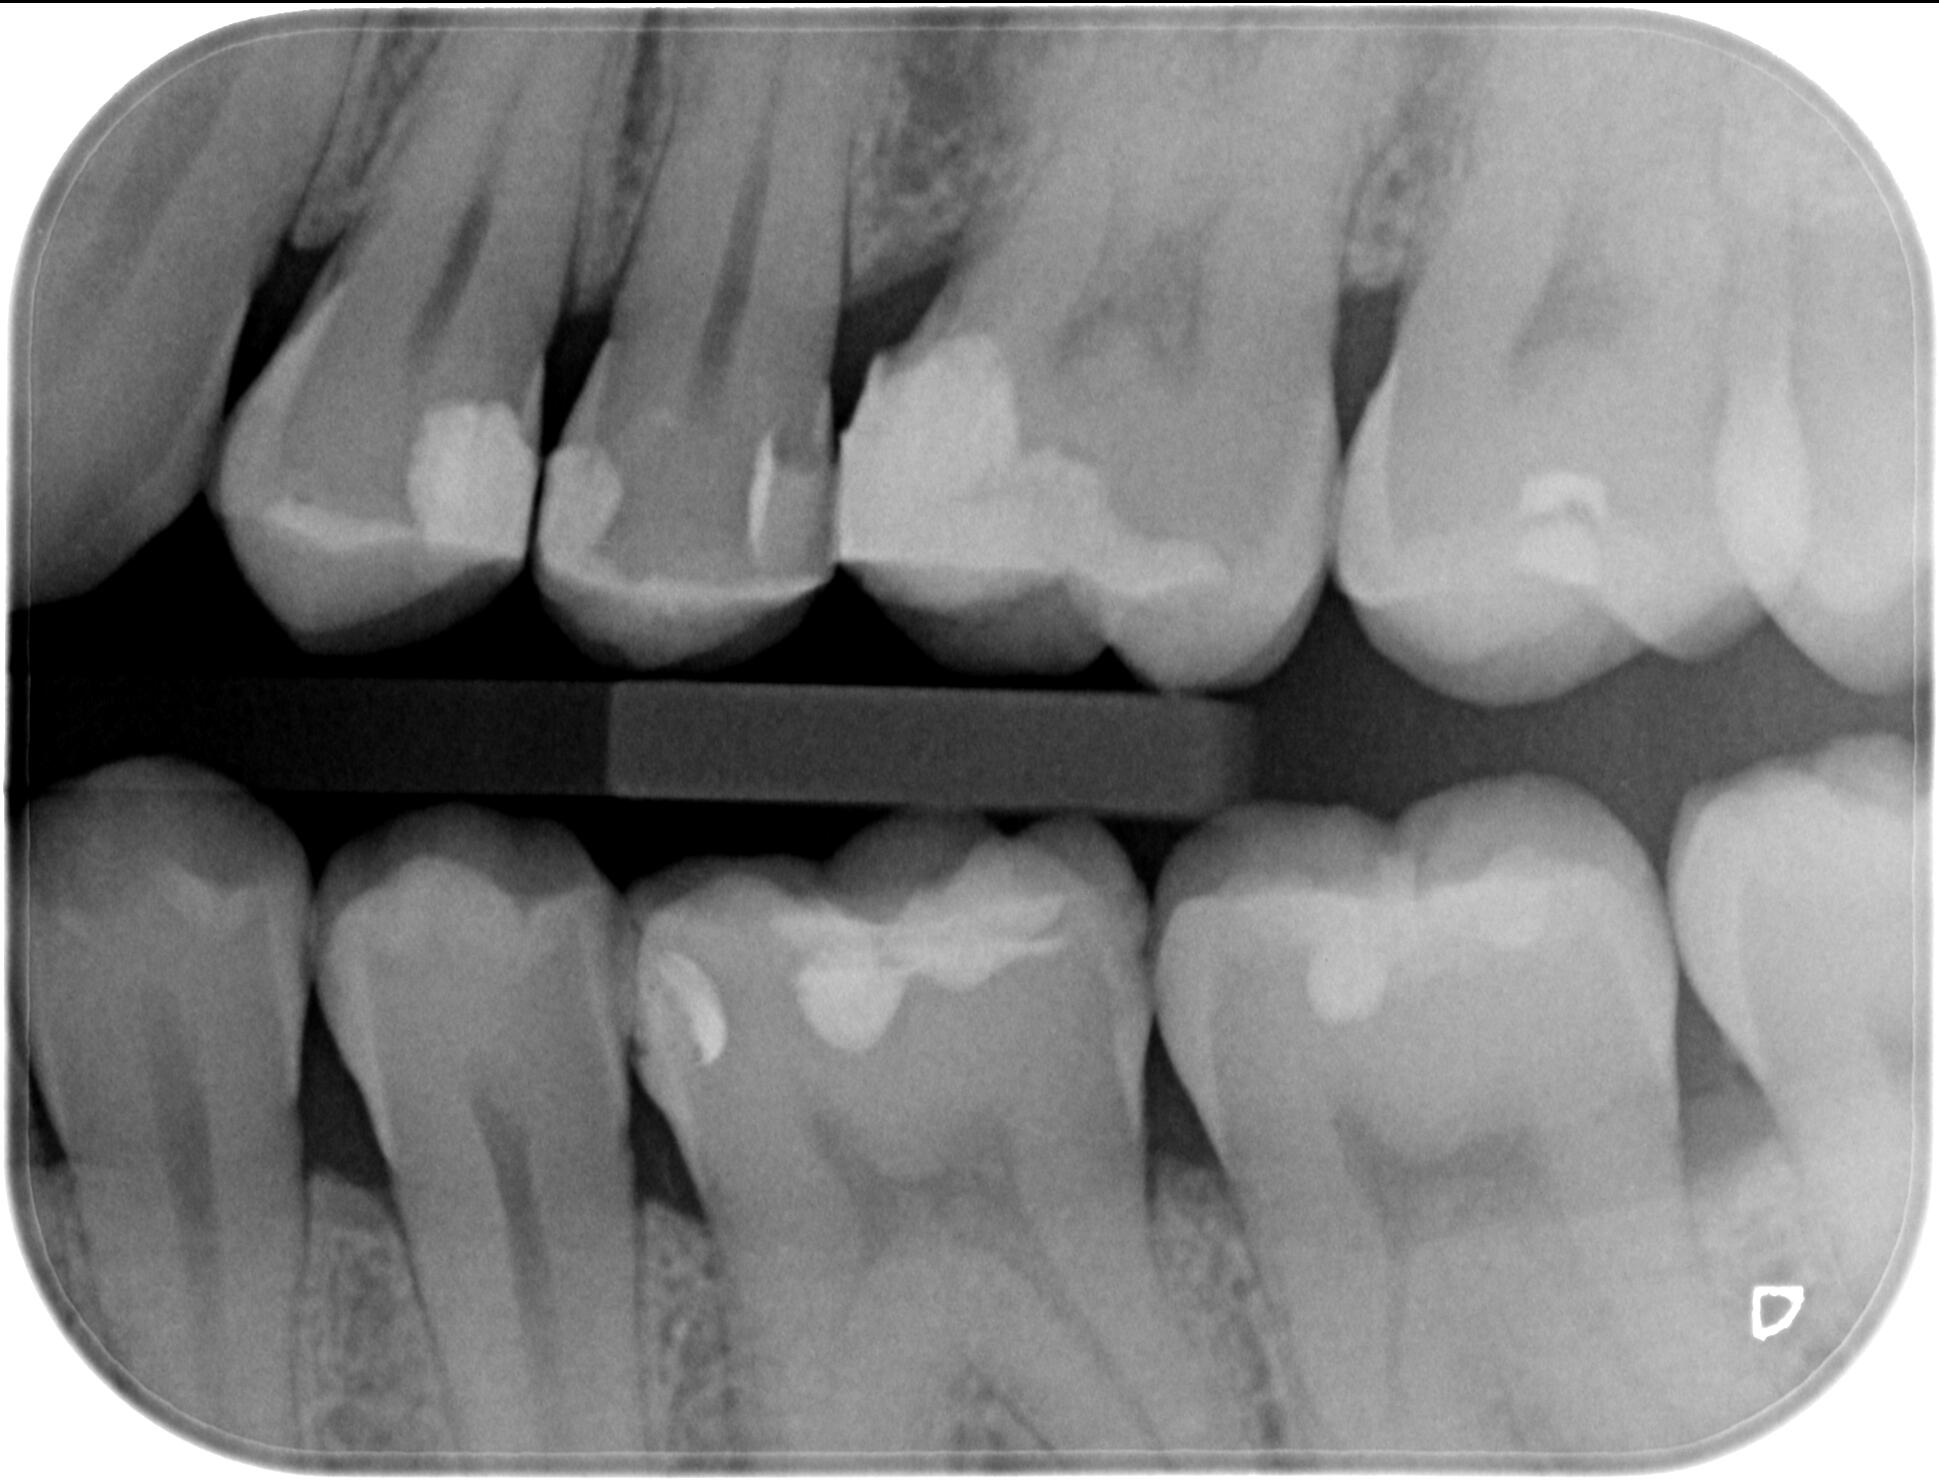

Байтуинг / Bitewing - кариес диагностика

Интраорален рентгенов апарат, характеризиращ се с бързо и лесно позициониране при изследване, за максимален комфорт на пациента.

За още по-голяма безопасност на пациентите, интраоралният ни рентген е оборудван и със специален тубус, който фокусира рентгеновите лъчи само в мястото, което искаме да бъде диагностицирано!

Dürr VistaScan

VistaScan е дигитален скенер за интраорални фосфорни плаки. Те са:

- с висока разделителна способност.

- меки и гъвкави, наподобяващи конвенционалните рентгенови плаки.

- обработват се за няколко секунди.